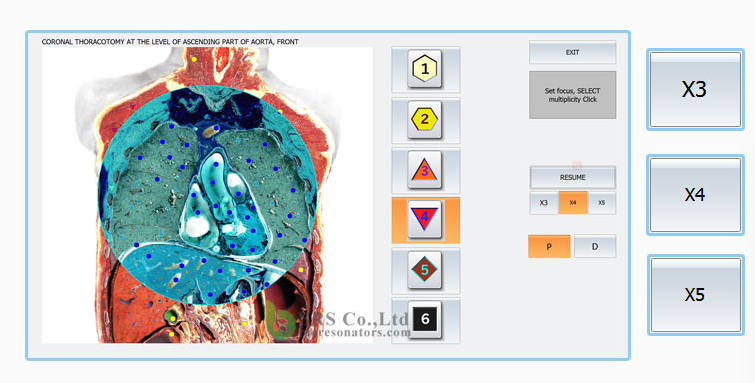

Високо ниво на визуализация: позволява в момента на изследването да се види точното местоположение на проблема

– Диагностичният процес е много по-лесен и резултатите са ясни веднага: общата продължителност на един сеанс е към 40 мин.

-Интуативен и лесен за употреба интерфейс на програмата

Методът, който използва “ Биофилия“ е биофизичен. Специални импулси идващи от 8 сензорна камера на апарата, въздействат на нашето тяло. Тези импулси поемат информация от тялото и я използват за тестване и установяване на здровословното състояние.